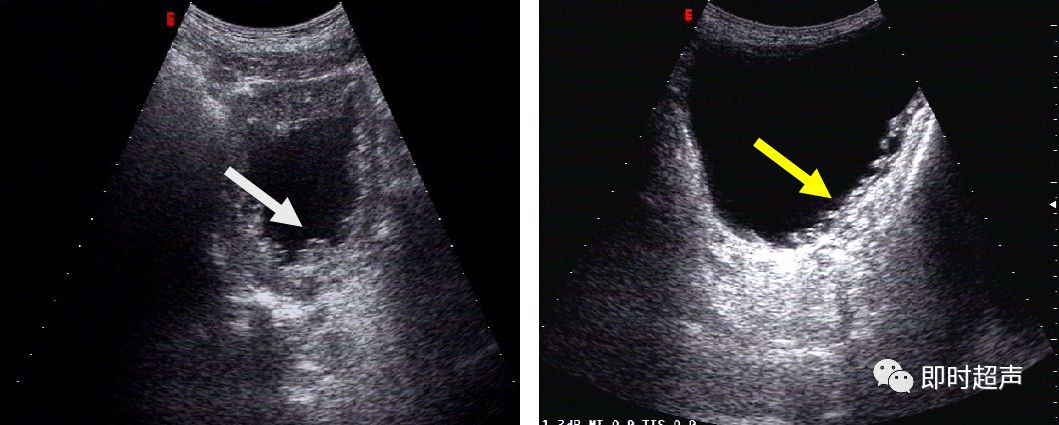

慢性膀胱炎膀胱壁呈“小梁状”结构 (箭头)弥漫性增厚结构(黄箭头)

膀胱内部可见散在的密集的点状强回声(箭头),有漂浮感

慢性炎症膀胱壁粘膜层不光滑(箭头)

膀胱结石:无回声暗区内团状强回声(箭头),后方伴声影(黄箭头)当体位改变时随体位移动